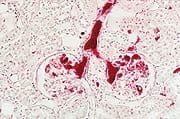

The link between cancer and genetic mutation has become much clearer in the past several years, with the discovery of tumor suppressor genes and proto-oncogenes. Tumor suppressor genes keep cell division within normal bounds, while proto-oncogenes drive the process of cell division forward. Mutations to either type of genes can result in cancer—the uncontrolled growth of cells.4,5 The list of diseases attributable to somatic mutation is growing rapidly.1 This is why it is so vitally important to block gene and DNA mutations during our lifetime using targeted antimutagenic agents. Among the most powerful mutation-blocking agents is chlorophyllin.6,7 Chlorophyllin is a semi-synthetic, water-soluble form of the plant pigment chlorophyll. Unlike some herbal ingredients that indicate cancer protection at high doses (hundreds of milligrams per kilogram of body weight in animal or human studies), chlorophyllin possesses anti-cancer and DNA damage-protection effects at much lower amounts. In fact, 40-100 mg of chlorophyllin three times daily is all many humans need to duplicate studies showing excellent protection against a wide range of dietary compounds that are known to cause cancer in humans and animals.8,9 Here, we’ll explore the latest research on chlorophyllin’s numerous health-promoting effects—from prevention of cancers caused by diet to managing a serious disease called leukopenia.8,9 Neutralizing Dietary Carcinogens and Preventing Multiple CancersAs Life Extension Magazine® first pointed out over a decade ago, the integrity of human DNA is under constant assault owing to the way we cook our food. Well-done meats—grilled, fried, or barbecued beef, pork, and chicken with skin—contain varying quantities of the powerful carcinogens benzopyrene and PhIP (2-amino-1-methyl-6-phenylimidazo [4,5-b] pyridine).8,10-12 Baking or stewing meat at moderate temperatures has not been shown to produce cancer-causing chemicals. These cancer-causing agents are ubiquitous. Benzopyrene is so commonplace and poses such a threat to human health that some countries test all imported foods for benzopyrene content. In sufficient quantities, this potent carcinogen binds to DNA, causing severe genetic mutation in affected cells. Once these cells divide, they can become precancerous—or cancerous.13 Chlorophyllin appears to counter benzopyrene’s carcinogenic effect in four distinct ways:

Chlorophyllin operates along similar biological pathways to neutralize other dietary carcinogens, including PhIP and aflatoxin from molds.8 By binding with them, it inhibits their absorption and speeds their transit through the gastrointestinal tract. This reduces adduct formation and tumor growth. 19-21 Similarly, its effects on phase I and phase II liver enzymes de-activate these dangerous agents22 and help the body to excrete them.16,17 Chlorophyllin’s unique capacity to halt the mutagenic activity of these carcinogens—and dramatically reduce incidence among numerous types of cancer—have been documented in a wealth of studies.

Liver CancerChlorophyllin’s anti-cancer effects were documented in a clinical human trial, conducted in Quidong province, China by a team from Johns Hopkins Bloomberg School of Public Health.8 Quidong has one of the highest recorded liver cancer rates in the world. Among other factors, crops infected with aflatoxin-producing fungus cause early death from liver cancer. People there live an average of 50 years and many die a painful death from liver cancer—one of the least treatable cancers.

Among the 180 people who took 100 mg of chlorophyllin three times daily in the Johns Hopkins study, urinary levels of DNA-aflatoxin adducts went down 55% compared to untreated people.8 The formation of DNA adducts often leads to DNA mutations and the formation of a cancer cell. A drop in DNA mutation rates such as would be expected from the participants in this study could delay the onset of cancer by as much as twenty years.23 Colon CancerThe most abundant carcinogen in fried meats, PhIP is a heterocyclic amine compound.24 These form when amino acids (the building blocks of proteins) and creatine (a chemical found in the muscle tissue) react at high temperatures. When PhIP is administered to laboratory animals, it speeds the development of aberrant crypt foci, the structural precursors of colon cancer. Mounting scientific research clearly indicates that chlorophyllin can help protect the colon against this lethal carcinogen. In a recent study, it cut the number of pre-cancerous aberrant crypt foci by 50% and accelerated the elimination of unmetabolized PhIP.12 In 2008, chlorophyllin was shown to inhibit the mutagenic effect of another heterocylic amine found in cooked meat and other foods called IQ (2-hydroxyamino-3-methylimidazo [4,5-f] quinoline). Researchers found that chlorophyllin rapidly degraded IQ’s mutagenic metabolite, potentially interrupting the development of colon cancer at an early stage.25 In another study, mice were given dimethylhydrazine, a carcinogen shown to specifically induce tumors in the colon. When chlorophyllin was administered concurrently, it prevented the formation of tumors by inhibiting the protein complexes that enable mutant DNA to replicate.26 Breast Cancer